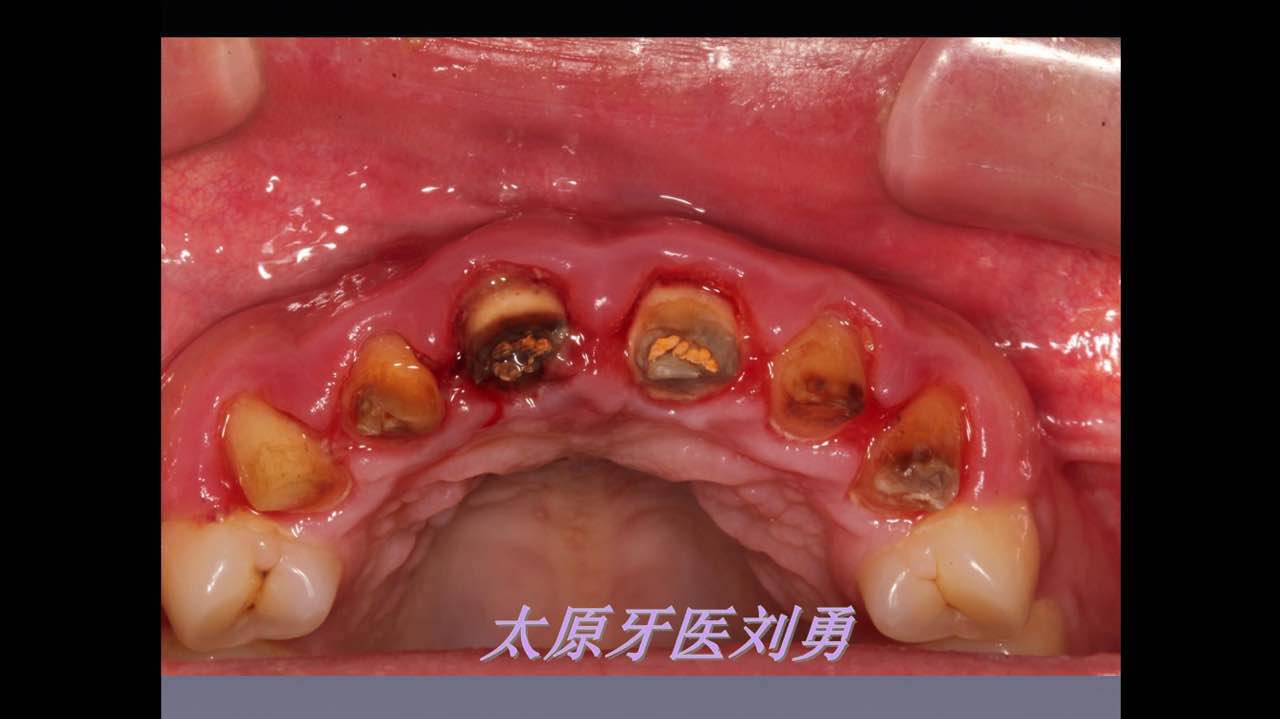

嚴重破壞生物學寬度,根尖瘺管,重行根管治療, 第一次冠延長建立唇腭側(cè)及鄰面BW,術后牙齦扇貝形差, 齦乳頭黑三角,再次行美學冠延長,建立牙齦扇貝形,手術免費, 患者因經(jīng)濟原因只能選擇鑄樁及鈷鉻合金烤瓷冠。終于完工